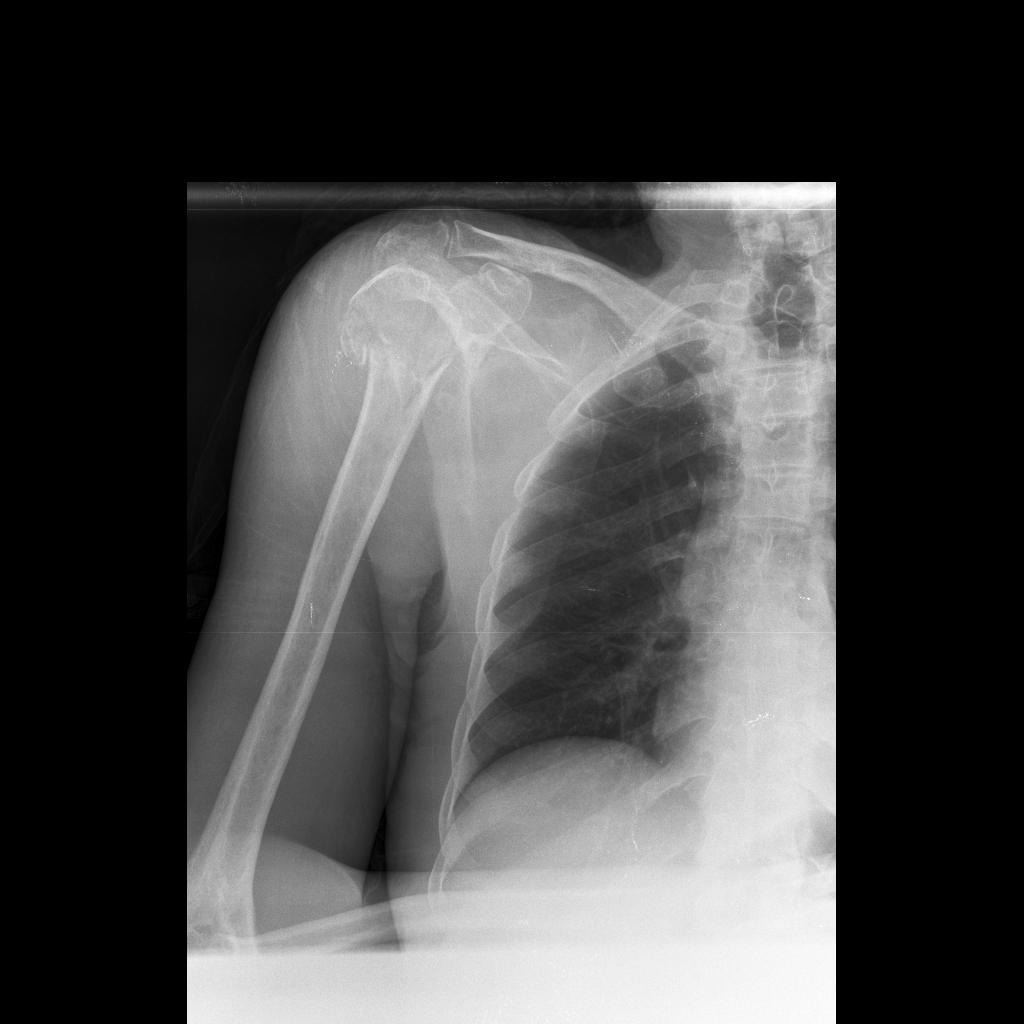

What type of injury can be seen?

Surgical neck fracture

What happens during a anterior dislocation of the shoulder?

the humeral head comes to lie anterior, medial and somewhat inferior to its normal location and glenoid fossa